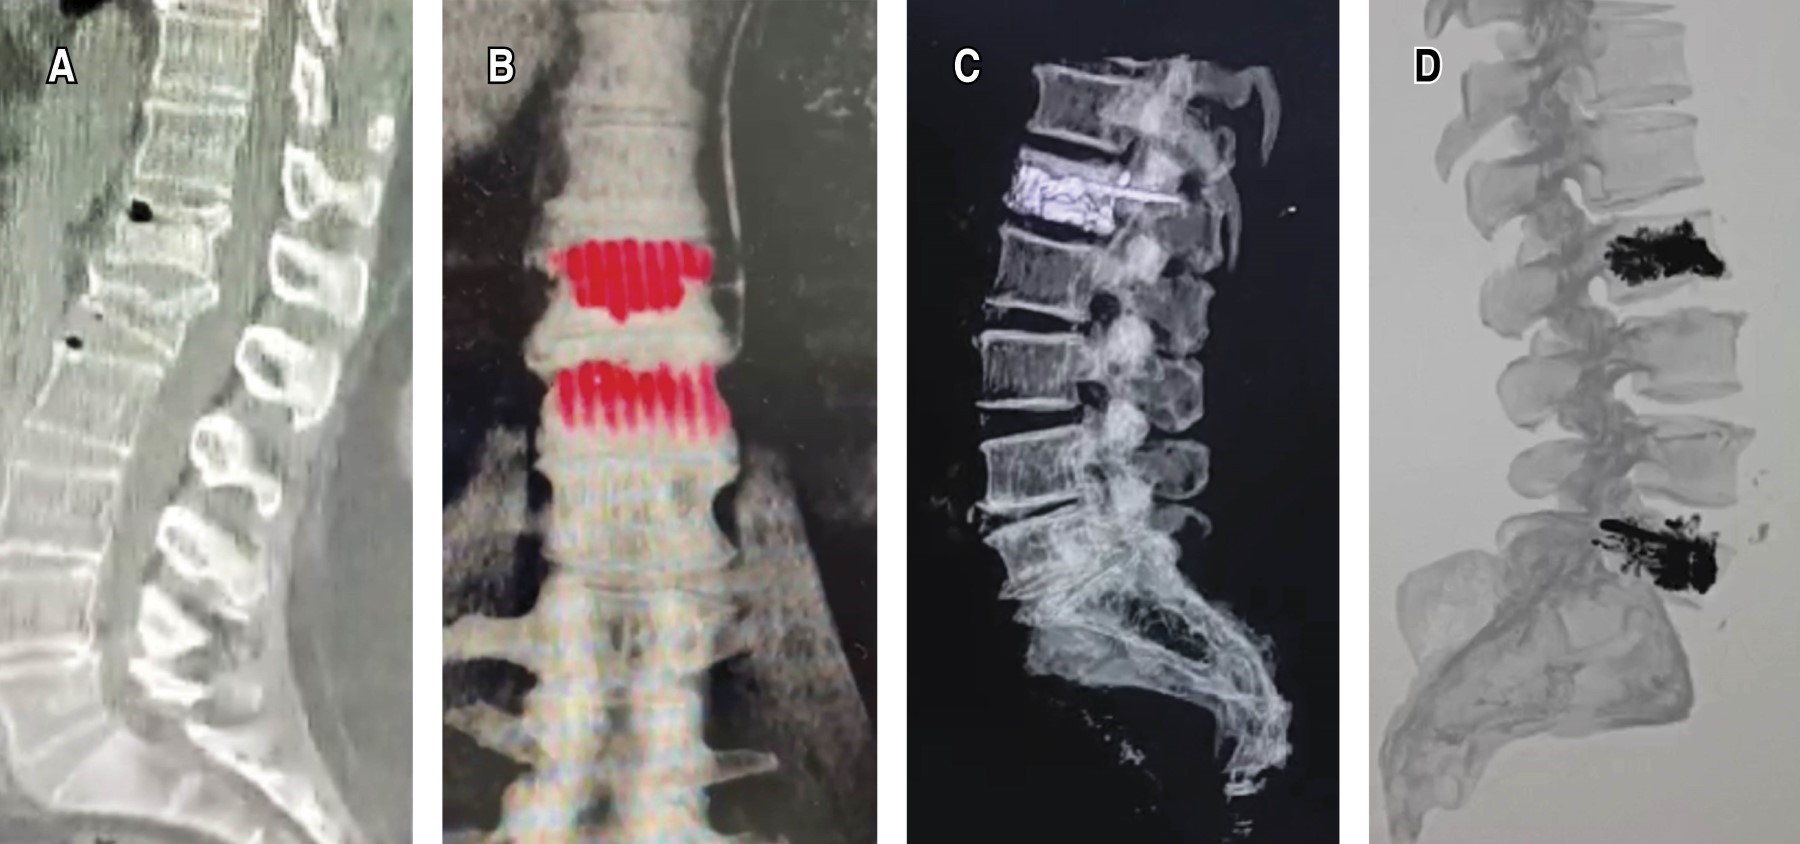

De forma paralela al dolor, se documentó una mejoría sustancial en la función y calidad de vida tras la cifoplastía, evaluada mediante el ODI. Preoperatoriamente, el porcentaje en el ODI era en promedio 88.8% ± 6.5 (indicativo de discapacidad grave). Tras la intervención, el ODI disminuyó a 25% a las 24 horas, lo que representa una mejoría inmediata de aproximadamente 64 puntos porcentuales (reducción absoluta de 44 a 12 puntos de 50, p < 0.001). Todos los pacientes mostraron disminución de su puntuación ODI en el postoperatorio temprano, cambiando en muchos casos desde categoría de "discapacitado severo" a "discapacidad moderada" en un solo día. Esta mejoría funcional continuó mejorando ligeramente con el tiempo. Al tercer mes postcirugía, el ODI promedio bajó a 24%, y a seis meses 22%. Para el año postprocedimiento, el ODI promedio fue 21.4% ± 8.1 (aproximadamente 10.7 ± 4.0 puntos de 50). Es decir, en un año se logró en promedio convertir una condición de discapacidad grave (88% de limitación) en una de discapacidad moderada-leve (21%) (Figura 3). En seguimientos prolongados, conforme los pacientes continuaron con rehabilitación y tratamiento de la osteoporosis, la funcionalidad siguió mejorando: a dos años el ODI promedio fue 9.7% (discapacidad mínima) y en los pacientes evaluados a 5-10 años fue 2.7%, acercándose a una independencia completa.

La incidencia baja de complicaciones observadas en nuestro estudio refuerza el perfil favorable de seguridad del tratamiento combinado (Figura 5). La fractura vertebral adyacente fue la complicación más común, lo cual es congruente con estudios previos que documentan que la redistribución biomecánica tras estabilizar una vértebra fracturada puede aumentar ligeramente el riesgo de fracturas en vértebras adyacentes. A pesar de ello, la incidencia observada de 8% está dentro del rango esperado según la literatura existente.31,32 La baja incidencia de fuga de cemento (3%) y su ausencia de relevancia clínica significativa, coincide con estudios previos que reportan que esta complicación, aunque relativamente frecuente en procedimientos vertebrales con cemento, raramente produce complicaciones clínicas significativas.33-35 La ausencia de infecciones postoperatorias refleja el éxito en la adherencia a protocolos estrictos de asepsia y profilaxis antibiótica.36,37 Este resultado destaca aún más la seguridad del procedimiento combinado, especialmente en pacientes de alto riesgo debido a múltiples comorbilidades.